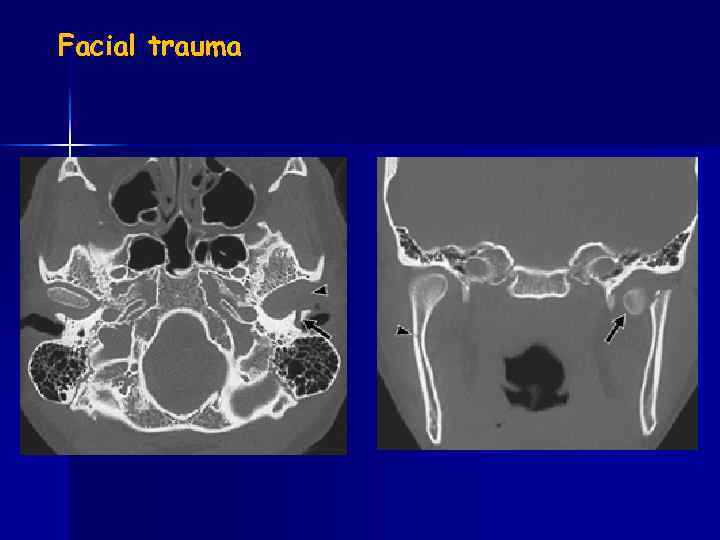

Facial trauma

Facial trauma blow-out fracture